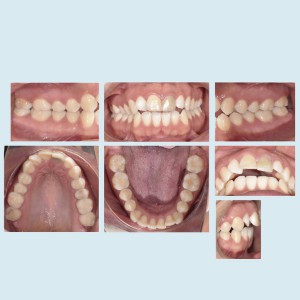

SERVICIOS 2D

SIALOGRAFIA

• Glándulas parótidas y sub maxilares